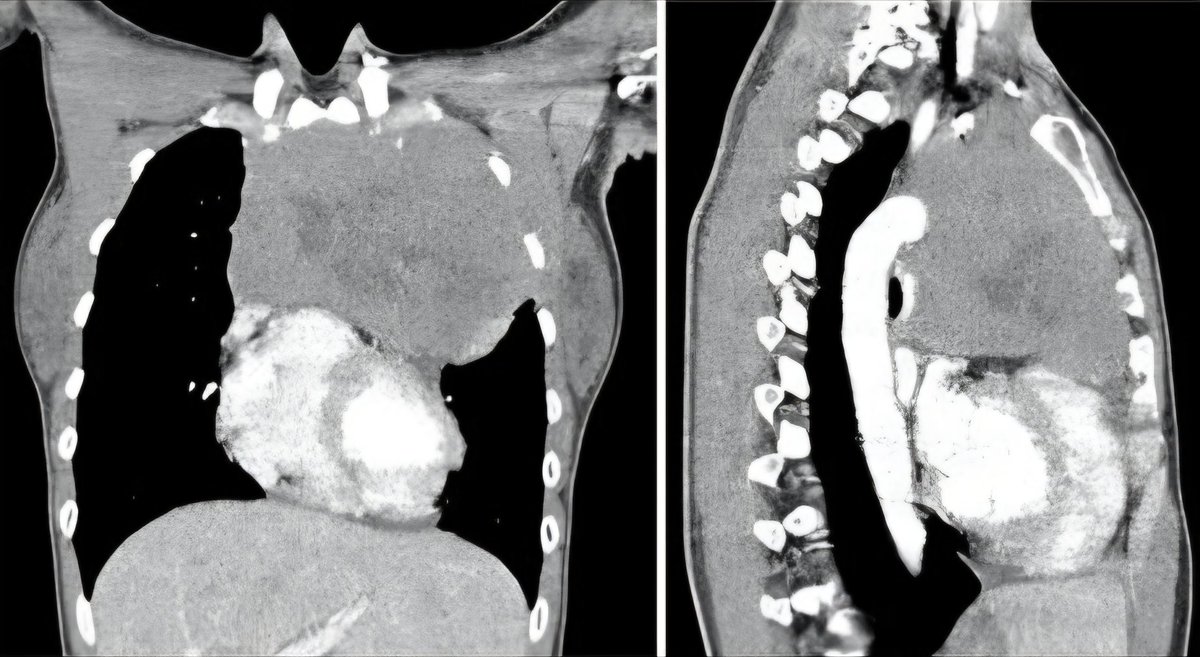

ليس كل ارتجاع مرئ سببه جرثومة المعدة ! Dr.Hasan Robaidi د. حسن ربيدي #الصحة #منصة_دكتوري #معلومة_طبية #استشاري #ارتجاع #جرثومة #المعدة